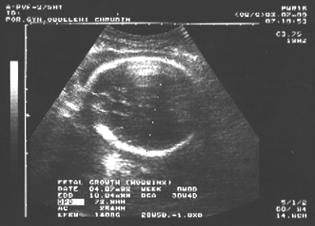

13. týden